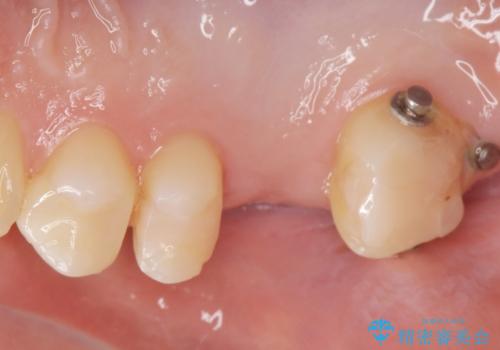

なので親知らずを抜歯して、一番奥の歯を部分矯正(upライト)をして倒れ込んでいる歯を起こしてスペースを作り、ブリッジの治療を行いました。

適合の良いブリッジが入りました。

歯の傾きを改善することにより食べ物が詰まりにくくなりました。

白い被せ物が入り、満足して頂けました。